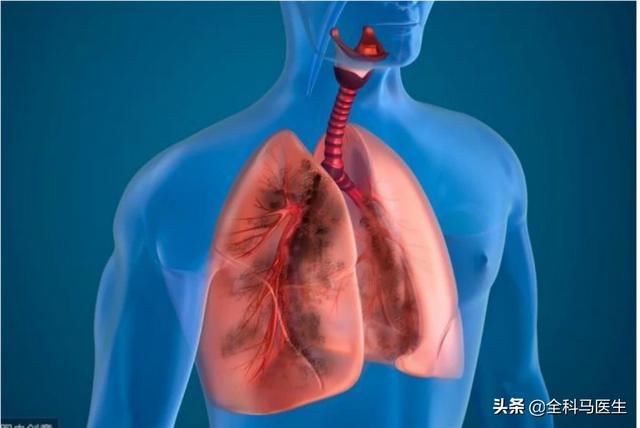

Pourquoi le tabagisme à long terme prédispose-t-il au cancer du poumon ?

Cela est principalement dû au fait que le tabac peut produire plus de 7 000 types de substances chimiques au cours du processus de combustion, et qu'il existe des centaines de substances nocives, dont plus de 60 types de substances cancérigènes, parmi lesquelles la nicotine est un agent cancérigène de première catégorie. Selon les données, la quantité et la durée du tabagisme sont directement proportionnelles à l'apparition du cancer du poumon, c'est-à-dire que plus l'âge du fumeur est jeune, plus la durée du tabagisme est longue et plus la quantité de tabac fumée est importante, plus l'incidence du cancer du poumon sera élevée, et l'incidence du cancer du poumon chez les fumeurs est des dizaines, voire des centaines de fois supérieure à celle des non-fumeurs.

Lorsque nous fumons pendant une longue période, les substances nocives contenues dans le tabac entraînent la prolifération des cellules épithéliales bronchiques, de l'épithélium pavimenteux et d'autres tissus, à partir desquels un carcinome épithélial pavimenteux ou un carcinome indifférencié à petites cellules peut être facilement induit.